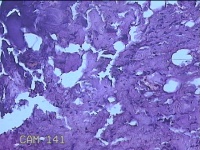

外阴部包块

性别

女

年龄

28岁

临床诊断

1.疖肿病 2.皮脂腺囊肿

一般病史

外阴部起丘疹疼痛一周。

标本名称

大体所见

灰白暗红色包块1x0.7x0.3cm一个,表面糜烂。